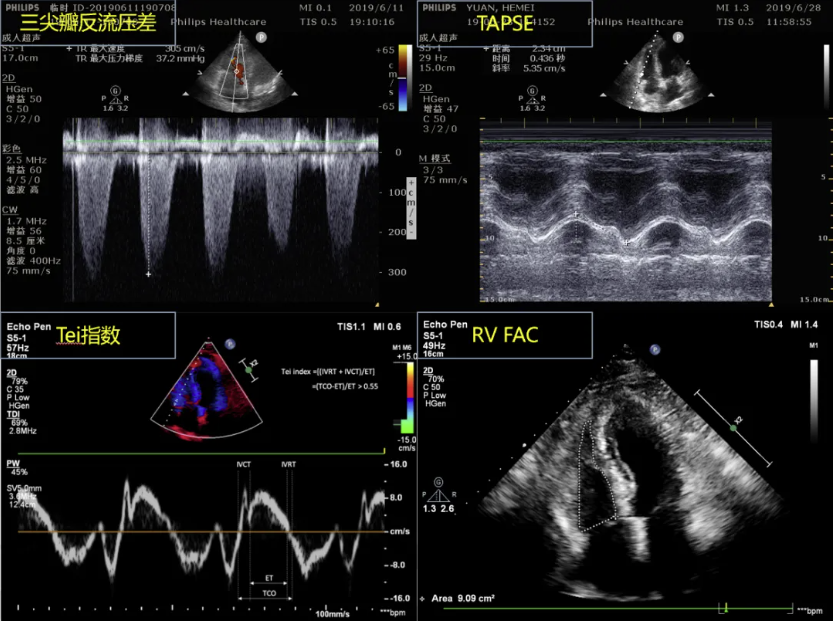

超声心动图是监测ARDS患者右心功能不全的良好替代。这是经胸超声心动图(TTE)床旁评估右心室解剖结构功能的主要成像技术 [8]。

通过TTE评估ARDS患者的右心功能,可依据检查结果将其右心受累情况分为三个亚型:1.ACP:表现为右心室扩张(右心室舒张末期面积/左心室舒张末期,面积>0.6,若无法获取该比值则需目测评估右心室呈中至重度扩张),以及左心室短轴切面显示室间隔矛盾运动;2.右心室衰竭(Right ventricle failure,RVF):右室扩大合并体循环静脉充血(CVP≥8mmHg),若无法测量CVP则以下腔静脉(IVC)增宽为判定依据;3.右心室功能障碍:三尖瓣环收缩期位移(TAPSE)≤16mm [4]。